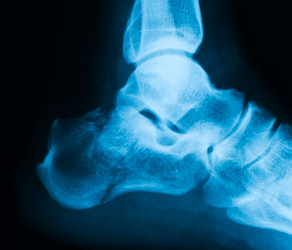

Zur Feststellung einer Sprunggelenkarthrose dient in der Regel eine Röntgenaufnahme. Auf einer solchen ist zu erkennen, ob sich der Gelenkspalt verkleinert hat oder freie Gelenkkörper vorliegen. Zudem können weitere Anzeichen für eine Arthrose identifiziert werden. So kommt es bei einer Arthrose zum Beispiel auch zu einer Anpassungsreaktion der beteiligten Knochen: Sie verdichten sich. Diese Verdichtung ist dann auch im Röntgenbild sichtbar.

Röntgenaufnahme des Sprunggelenks

Röntgenbild einer Arthrose